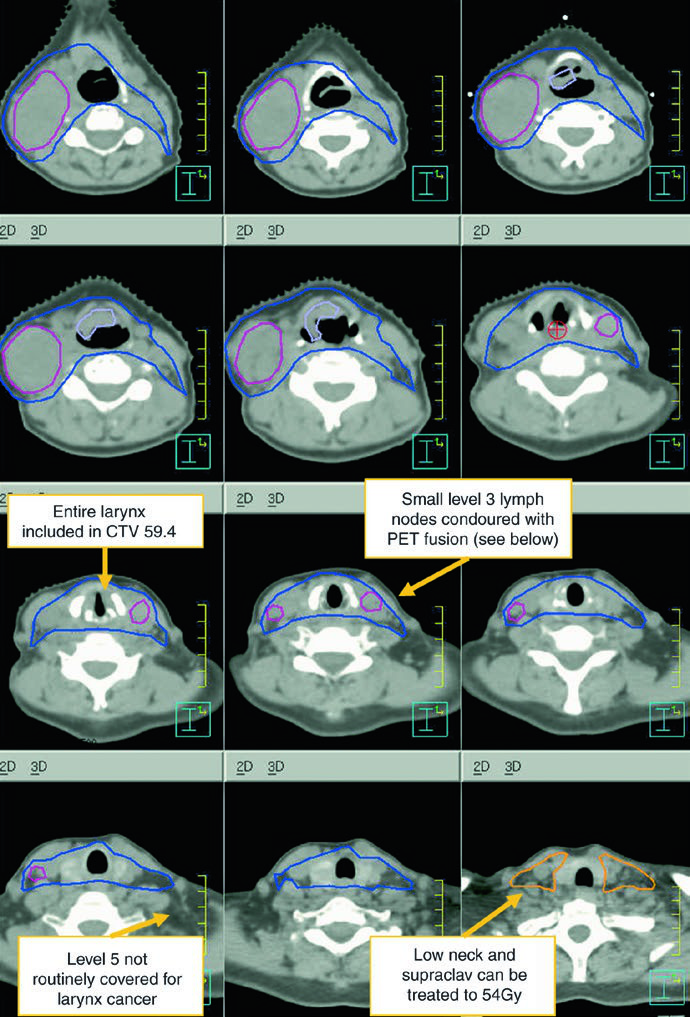

The subclinical primary CTV should cover the whole larynx from the bottom of the thyroid notch to the first tracheal ring, or farther inferiorly when needed. The subclinical nodal CTV should include at least levels II-IV and, in many cases, level VI. In the elective node-negative neck, the superior extent of level II stops where the posterior belly of the digastric crosses the internal jugular vein, corresponding to the caudal edge of the lateral process of C1. In the node-positive neck, level II should extend to the skull base and include the ipsilateral retrostyloid nodes.

| CTV 54-60a | Should encompass the entire GTV. Includes the entire larynx, from the bottom of the hyoid or the top of the thyroid notch to the bottom of the cricoid cartilage, with further inferior extension when needed. High-risk nodal regions include levels II-IV and the retrostyloid space on the involved node-positive neck. In the node-positive neck, level II should be treated to the base of skull. Level VI should be included if there is subglottic extension or a trach. |

| CTV 54b | Levels II-IV of the uninvolved neck. In the node-negative neck, the superior border of level II stops where the posterior belly of the digastric crosses the internal jugular vein, or at the caudal edge of the lateral process of C1. Levels IB and V are not included unless there is gross disease at those levels. Retropharyngeal nodes may be covered at physician discretion on the side of bulky adenopathy because of retrograde flow. Level VII coverage is recommended for subglottic extension or hypopharyngeal involvement. |

Levels IB and V are not elective by default and are only included when gross disease is present there. Retropharyngeal nodes may be covered on the side of bulky adenopathy at physician discretion. Level VII is recommended for subglottic extension or hypopharyngeal involvement. That is one of the most useful parts of the chapter because it turns abstract spread patterns into concrete cranial and caudal borders.

The figure caption adds two good reminders. In that example, level IB was included by the treating physician even though it can be omitted. The upper trachea was not treated, but the text notes that it should be included when indicated. That is a useful warning against copying a figure without rechecking the anatomy.